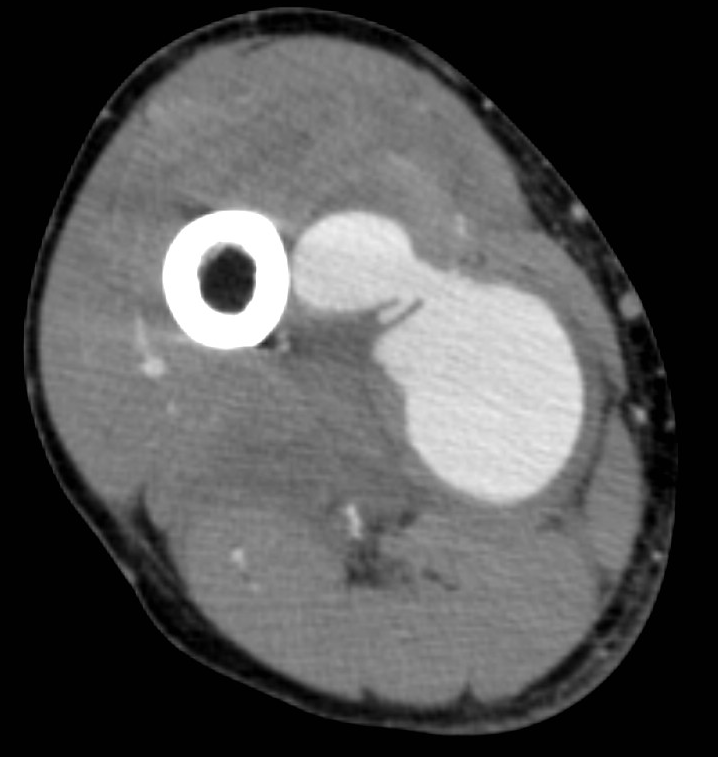

• A knife falling from a kitchen table stuck into the right thigh of an 18 year old young man. Increased femoral circumference and pulsating mass were seen. In the upper image with femoral Duplex sonography pseudoaneurysm of the femoral artery is detected

In the middle with a CT angiography the pseudoaneurysm shows contrast enhancement.

In the lower image 3D reconstruction of the CTA

11. A knife falling from a kitchen table stuck into the right thigh of an 18 year old young man. Increased femoral circumference and pulsating mass are seen. In the upper image with femoral Duplex sonography pseudoaneurysm of the femoral artery is detected In the middle with a CT angiography the pseudoaneurysm shows contrast enhancement. In the lower image 3D reconstruction of the CTA